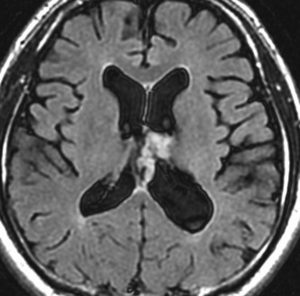

無症状で偶然発見された47歳女性の側脳室内上衣下腫

無症候で偶然発見された左側脳室前角尾状核頭に接したsubependymoma。定位脳生検で病理診断を得たましたが,3年間の観察で徐々に増大しました。左上が発見時,1年後(右上),2年後(左下),3年後(右下)

CTではやや低吸収,T1ガドリニウムでは低信号となりガドリニウム増強されません。小さな上衣下腫の場合は等吸収あるいは等信号のものも多いです。小さく点状に造影されている部分があるがこれは定位脳手術痕(track)です。

左中前頭回からの経皮室法 left middle frontal gyrus transcortical approach で全摘出できました(右図)。